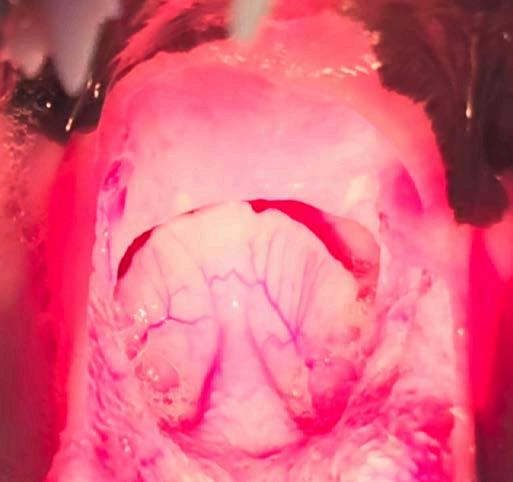

De acuerdo con los resultados obtenidos durante la observación de la epiglotis y el grado de obstrucción de la rima glottidis, la RE se clasifica en bajo y alto grado de obstrucción. Así, se definió como de bajo grado cuando la epiglotis se eleva de la lengua en el ciclo inspiratorio sin desplazarse ventralmente, lo que obstruye parcialmente la rima glottidis. En las RE de alto grado, la epiglotis se retroflexiona caudalmente en la inspiración dando lugar a una obstrucción completa, e incluso en algunos casos la punta se desplaza dentro de la rima glottidis19 como se aprecia en la Fig. 2.

Figura 2. Detalle de retroversión epiglótica de alto grado (retroflexión de la epiglotis en fase de inspiración con obstrucción completa de la rima glottidis).